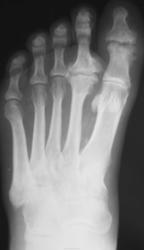

Подагра. Болезнь А. Келера II.

Келлера2, действительно. Но думаю, что 1 палец похож на остеомиелитный, тем более, что хорошо видны частично склерозированные сосуды. Что у пациетна с сахарами?

Есть дырочка падагрического тофуса у I пальца.

Келлер2. Остеомиелит или посттравматические изменения. Для подагры слишком круглый и без склероза.

Пробойники при подагре как раз круглые

Тогда гда медиальная стенка тофуса и ободок склероза?

По мне - остеофиты это все.